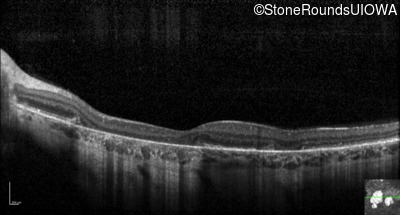

Optical Coherence Tomography - Right - 20/20 sc

Exemplar / OCT Stack